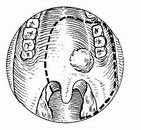

Marginální resekce mandibuly

Přední marginální mandibulektomie

Zadní marginální mandibulektomie

Tumory v těsné blízkosti čelisti

Minimální kortikální invaze

KI: bezzubá čelist, st. p. RT